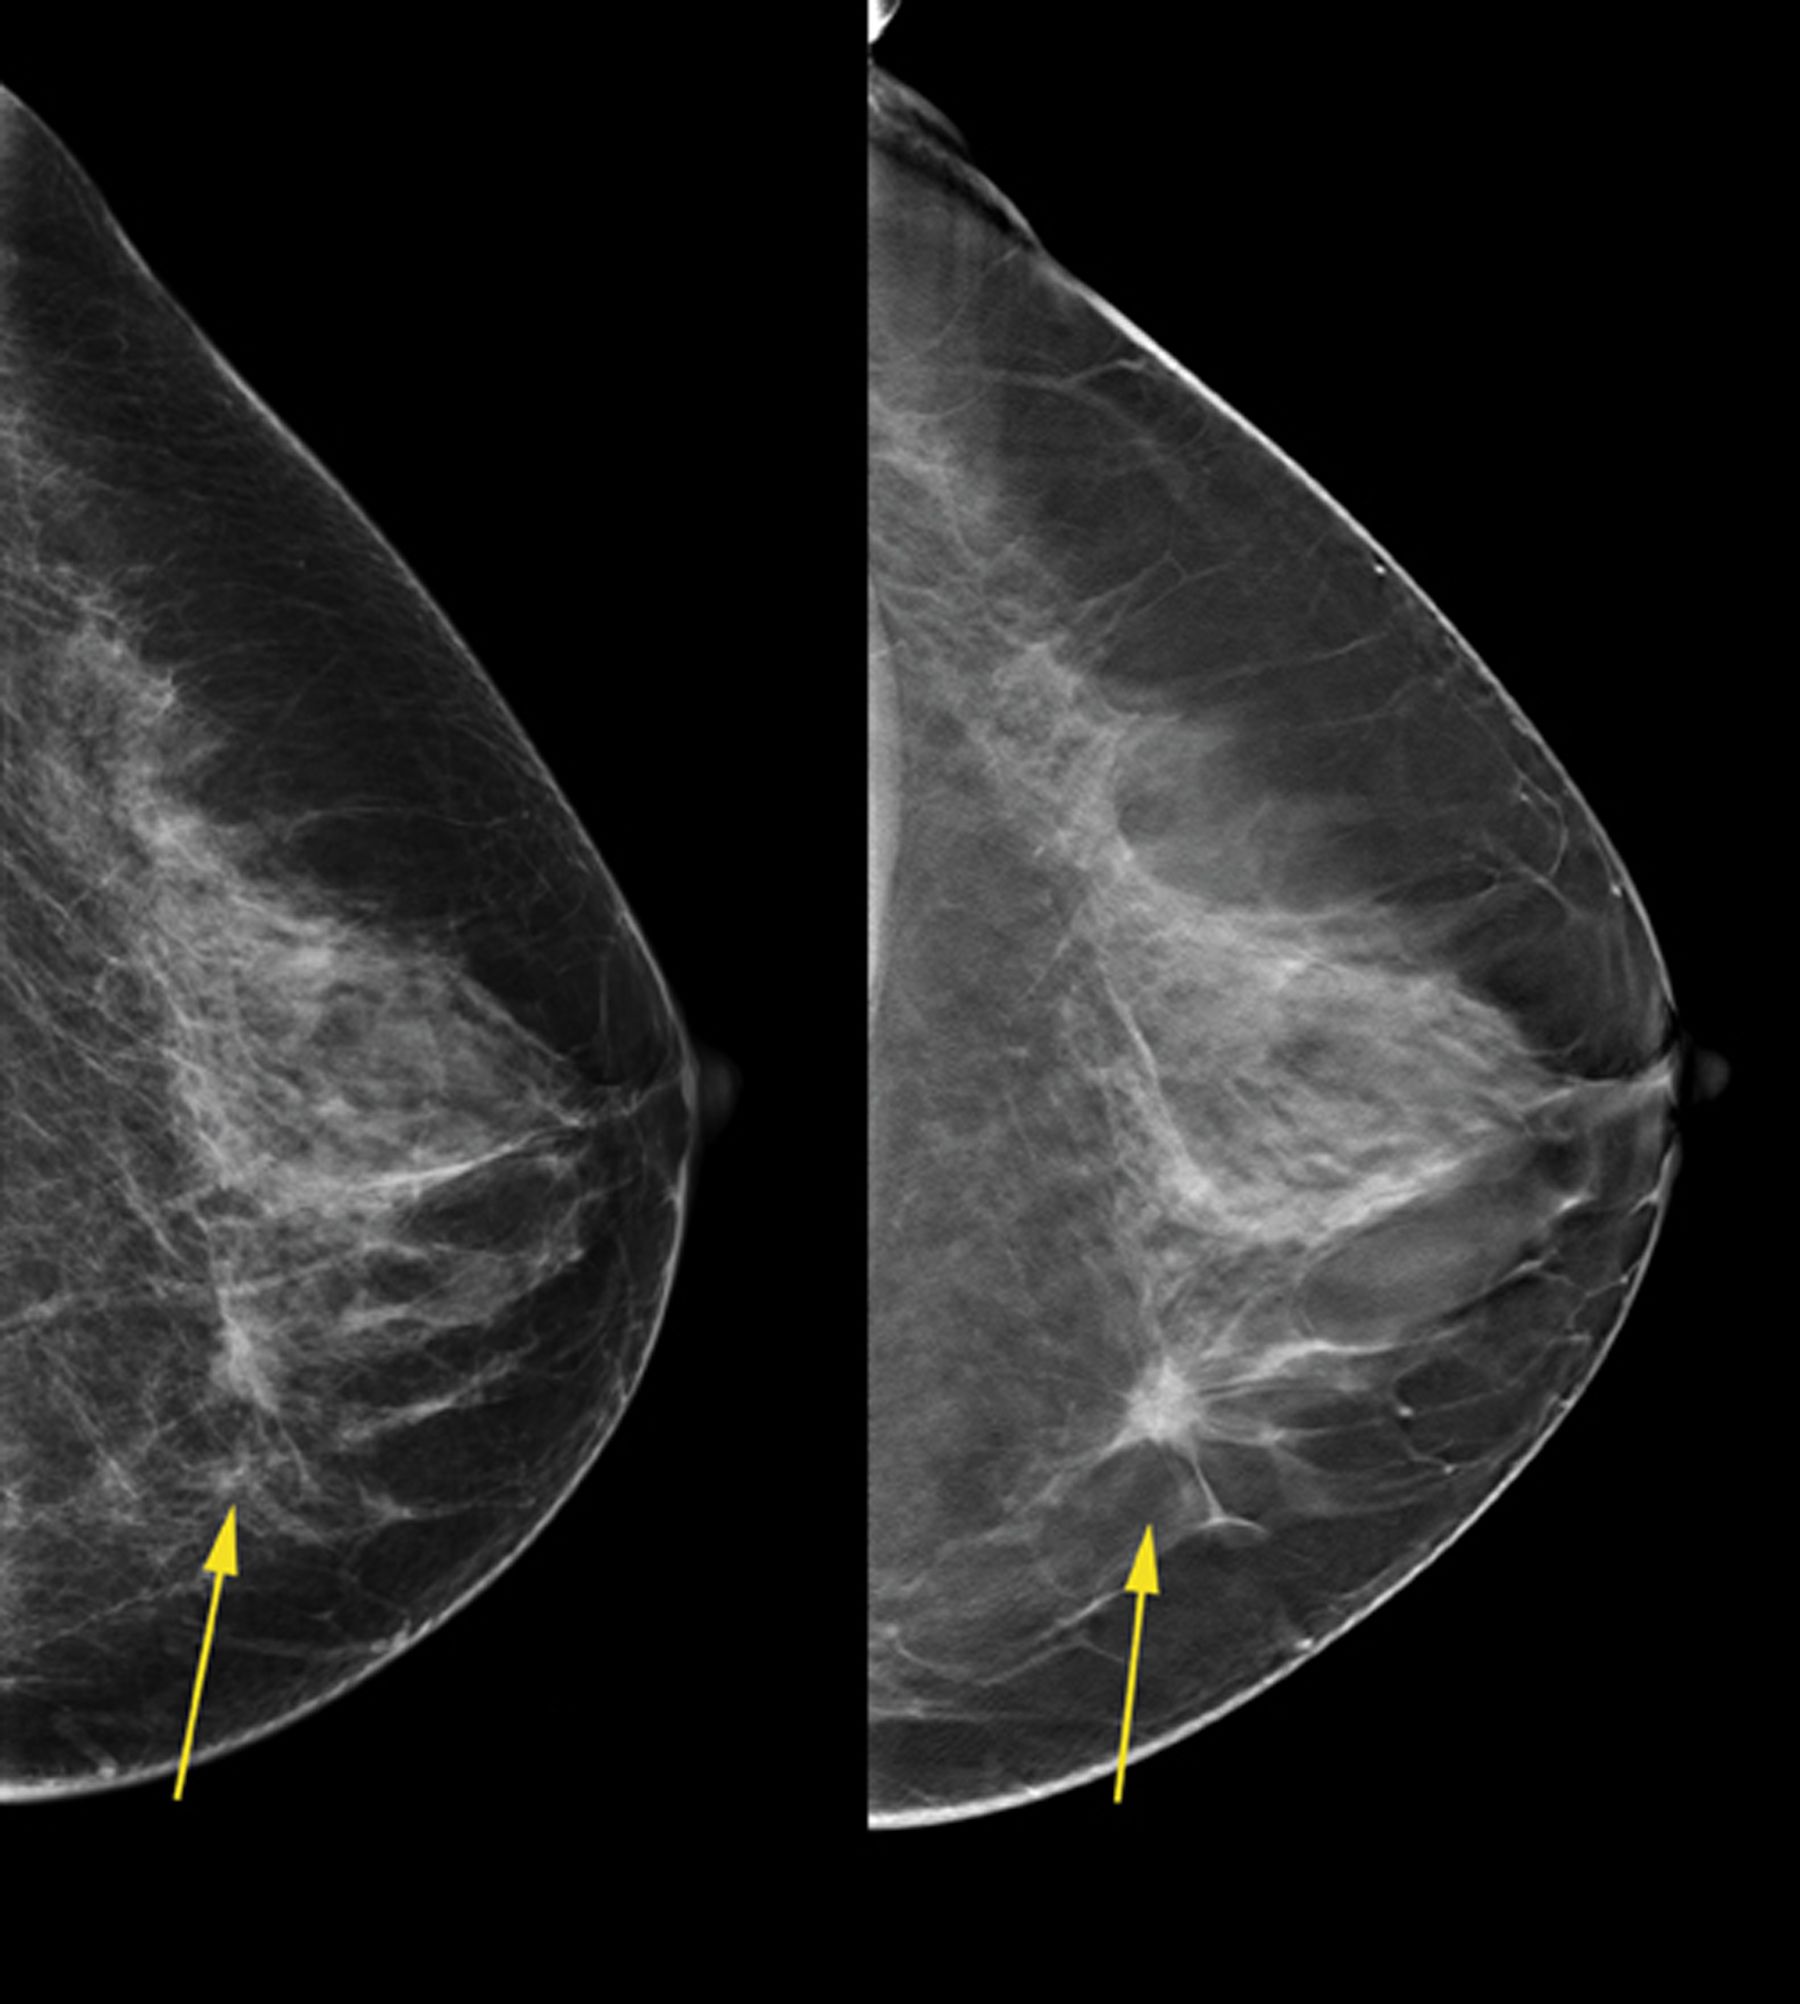

하지만 아직도 유방조영술이 완벽하지 않다고 전문가들은 지적하고 있습니다. 선별 유방 촬영술은 전체 유방암의 약 20%를 놓치는 경우가 있습니다. 그러나 최근 《랜싯 종양학》에 발표된 연구에 따르면 AI의 도움을 받으면 지금보다 더 안전하고 효과적으로 유방암을 발견할 수 있다고 합니다.

이 연구에서는 스웨덴 여성 8만여 명을 대상으로 2021년 4월부터 2022년 7월까지 유방 촬영술을 조사했습니다. AI와 함께 영상의학과 전문의가 사진을 판독한 그룹에서는 AI의 도움 없이 영상의학과 전문의가 판독한 그룹보다 약 20%나 더 많은 암이 발견되었습니다. AI와 함께 판독한 그룹의 암 발견율은 1000명당 6명이었던 반면, 전문의들만 판독한 그룹에서는 1000명당 5명이었습니다.

이 연구 결과로 보아 AI가 유방암 발견에 있어서 의사들의 능률을 높여줄 수 있을 것으로 기대됩니다. 유방암의 복잡한 패턴을 감지하는 것은 전문 교육이 필요하며 어려운 일입니다. 하지만 AI는 이미지를 분석하고 다양한 자료를 학습하여 더 정확한 예측을 내릴 수 있습니다. AI와 함께 사용함으로써 방사선 전문의들의 판독 작업량이 감소하게 되어 더욱 효율적인 검진이 가능해질 수 있습니다.